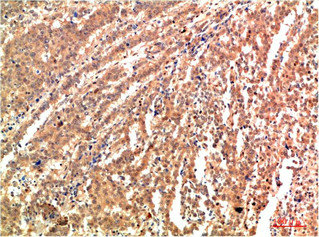

Immunohistochemical analysis of paraffin-embedded Human Lung Carcinoma Tissue using JNK2 Rabbit pAb diluted at 1:200